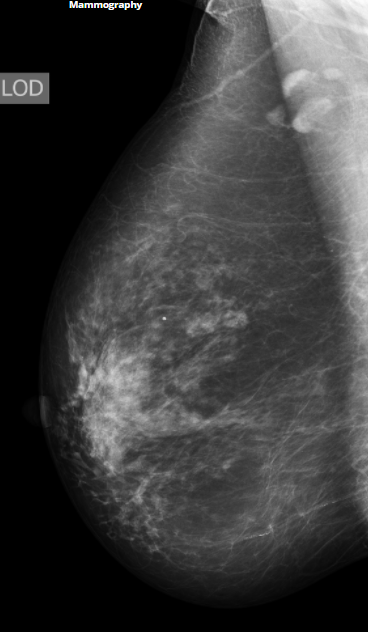

BIRADS 2

Conduta

A

Benigno-cisto

calcificação em pipoca

repete em 2 anos